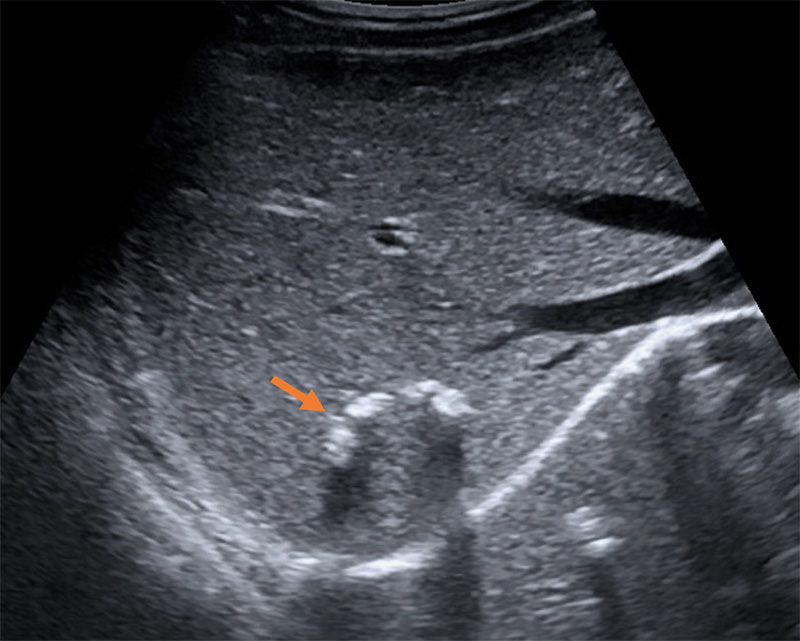

- Periportal fibrosis – thickening of the hyperechoic borders of the portal vein and branches.

Figure 54A. Transverse views of the liver revealing moderate periportal fibrosis. Note the thickened hyperechoic walls surrounding the portal vein and branches.

Figure 54B. Transverse views of the liver revealing moderate periportal fibrosis. Note the thickened hyperechoic walls surrounding the portal vein and branches.